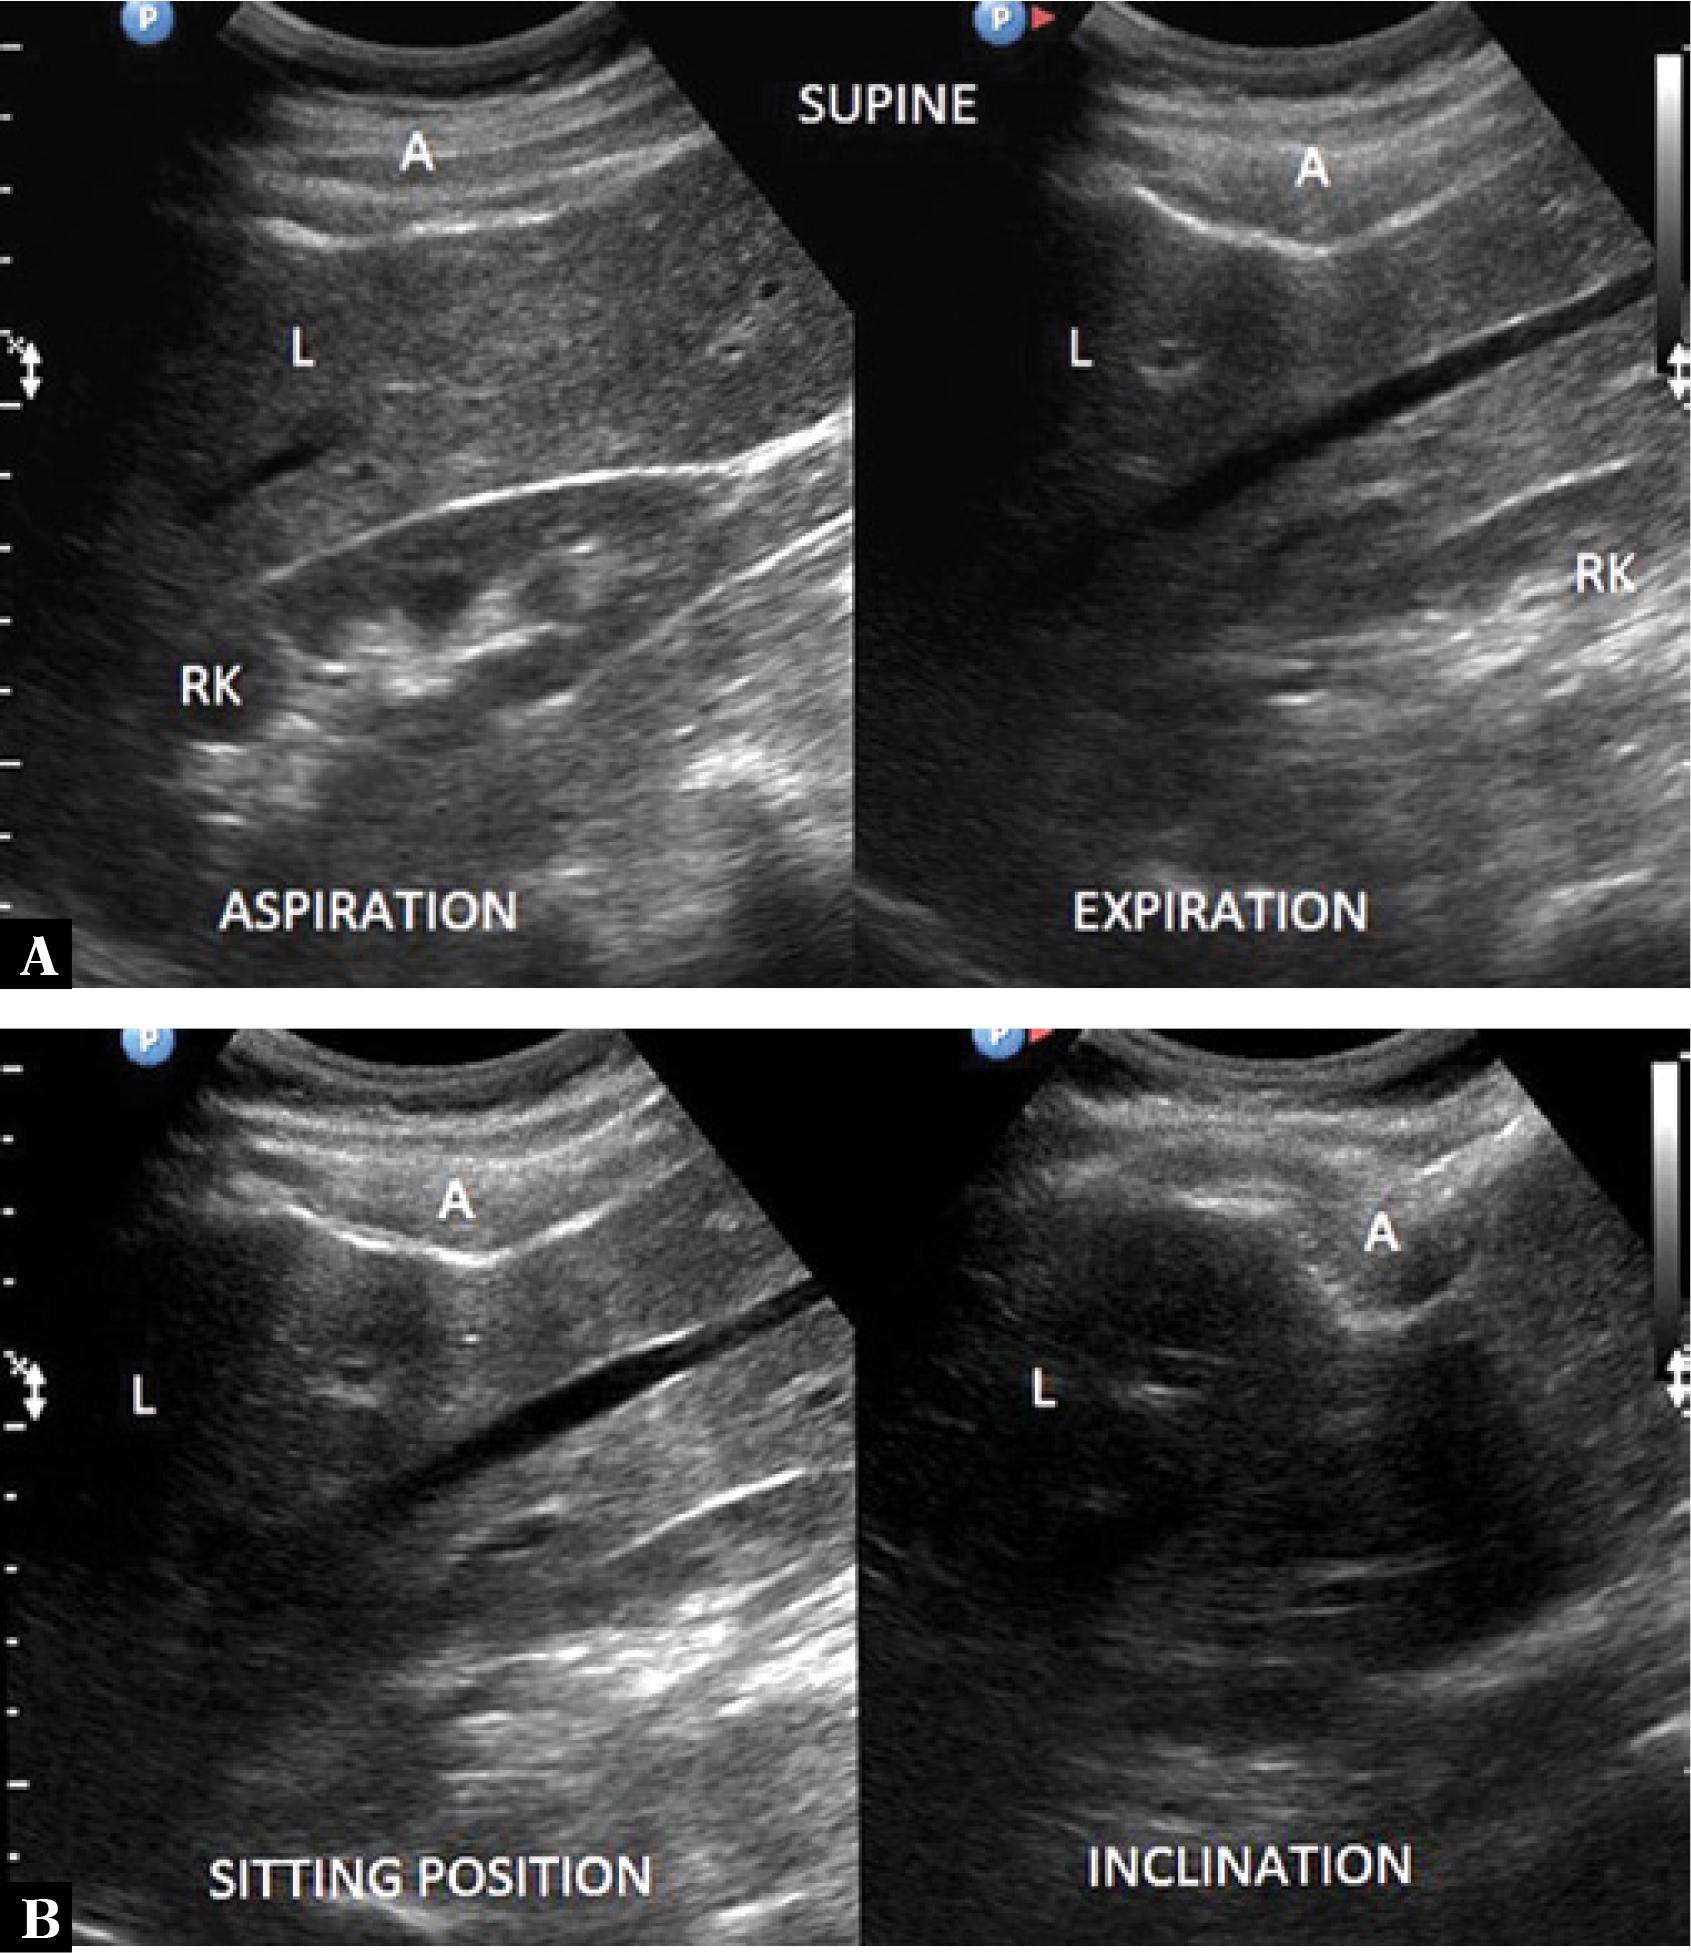

Fig. 3